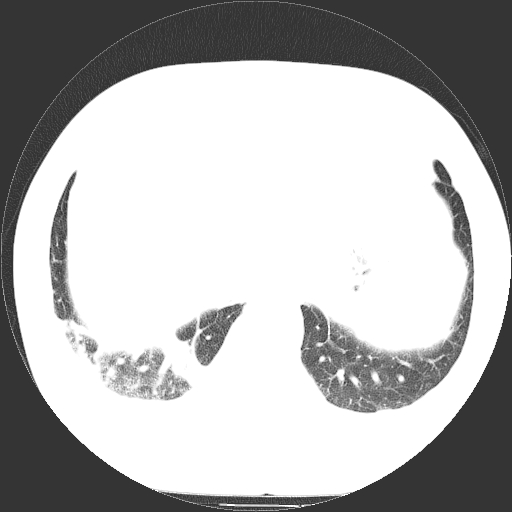

男,65岁,咳嗽、咳痰、发热5天。

慢支 肺间质纤维化合并感染!

支气管扩张合并感染,胸膜肥厚

考虑慢支并感染,肺间质纤维化。

两肺间质性炎症并感染

慢支,肺心病

支持慢性支气管炎伴感染,双侧少量胸腔积液.

两肺间质纤维化,支扩合并感染,双侧胸腔积液

感染,肺间质纤维化。

慢支 肺间质纤维化合并感染

支持慢性支气管、肺间质纤维化合并感染。

慢性支气管炎并感染,支扩,双侧少量胸腔积液.